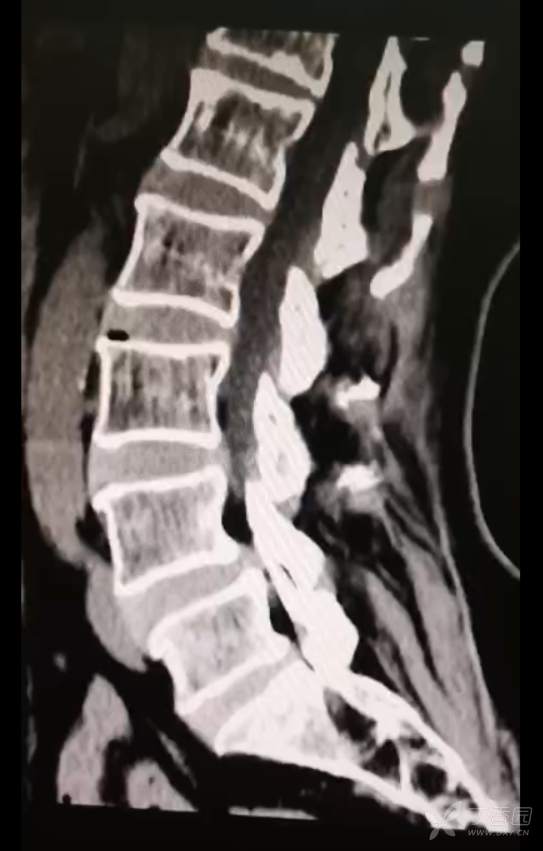

黄骨头脊柱内镜——腰4-5椎管狭窄侧路减压一例